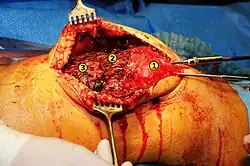

1. Kniescheibe

2. Abrissstelle am oberen Pol mit vorgelegten Bohrkanälen

3. Stumpf der Quadrizepssehne

Die Therapie der kompletten Ruptur ist in der Regel die Sehnennaht. Hierbei werden die Nähte meist, da der Riss häufig direkt am Kniescheibenansatz oder knapp oberhalb liegt, durch in der Kniescheibe angelegte Bohrkanäle geführt. Die Nachbehandlung besteht aus der primären Ruhigstellung des Kniegelenkes im Gips oder mittlerweile häufiger in einer Orthese. Mit letzterer kann nach vier bis sechs Wochen die Beugung des Kniegelenkes Schritt für Schritt in definiertem Ausmaß freigegeben werden. An die Freigabe der Beugung nach sechs bis zehn Wochen schließt sich eine intensive krankengymnastische Übungsbehandlung an, die zum einen der Kräftigung der mittlerweile atrophierten Oberschenkelmuskulatur, zum anderen der Förderung der Beweglichkeit im Kniegelenk dient.